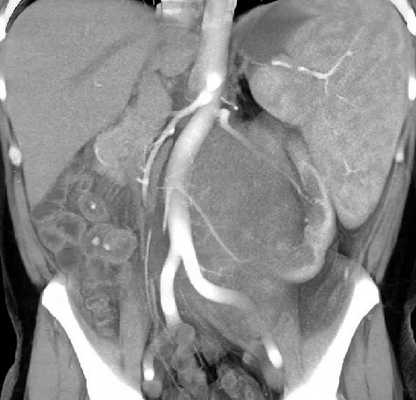

МРТ органов брюшной полости и забрюшинного пространства ‒ это безопасный и высокоинформативный метод исследования, который позволяет не только уточнить локализацию опухоли, точные размеры новообразования и соотношение его с окружающими тканями, но и выявить метастатические очаги в печени и брюшной полости. Также МРТ дает возможность оценить состояние костных структур и мягких тканей позвоночного столба и позвоночного канала (рис. 6).

Рис. 6. МРТ нейрогенного образования забрюшинного пространства слева